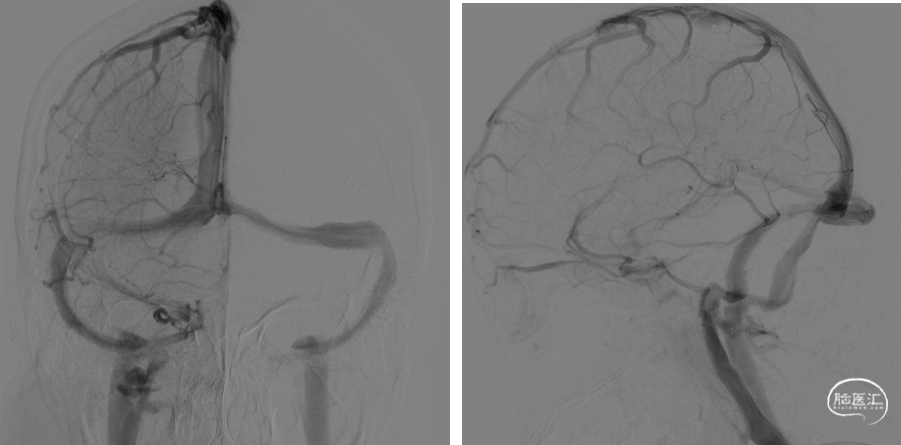

术前DSA:双侧横窦乙状窦交界处重度狭窄。

首先,建立右侧桡动脉通路,进行常规全脑血管造影,明确双侧横窦乙状窦交界区狭窄,排除动静脉瘘。再建立右侧股静脉通路,5F 125 造影导管与6F长鞘组成同轴系统,将长鞘置于右侧颈内静脉远心端。泥鳅导丝引导下将造影导管置于右侧横窦近窦汇处,通过造影导管行静脉窦测压,狭窄远端压力22mmHg,狭窄近端压力21mmHg,跨狭窄段压力差为1mmHg,故放弃右侧静脉窦支架植入术。

再利用同轴技术将6F 长鞘置于左侧颈内静脉远心端。尝试通过泥鳅导丝将造影导管置于左侧横窦失败,撤出造影导管,更换XT-27微导管,在Transend Floppy 300微导丝引导下顺利到达窦汇处。通过微导管进行静脉窦测压,狭窄远端压力26mmHg,狭窄近端压力18mmHg,跨狭窄段压力差为8mmHg,故决定行左侧静脉窦支架植入术。

撤除微导管,选用Precise 8*40mm支架,沿Floppy 300微导丝尝试将Precise支架越过狭窄段失败。撤出支架,沿Floppy 300微导丝将Tethys®中间导引导管顺利送达左侧横窦远心端。再利用特洛伊木马技术将Precise支架推送到位,回撤Tethys®中间导引导管,支架定位准确后成功于跨左侧横窦-乙状窦狭窄处释放。

在Tethys®中间导引导管下支架顺利通过左侧横窦乙状窦交界处

再次将XT-27微导管穿过支架送至横窦远心端,对支架远近端进行测压,支架远端压力22mmHg,近端21mmHg,压力差为1mmHg。复查造影提示左侧横窦狭窄显著改善,DynaCT未见颅内出血。遂结束手术。

术后即刻影像及患者术后情况:左侧横窦-乙状窦交界处狭窄显著改善,患者术后耳鸣较术前改善,视力无进一步加重,无头痛不适。

本例患者为一肥胖女性,以慢性进展性视力减退为突出临床表现,由于没有得到及时的诊断而引起了严重的双眼视力下降,右侧视神经甚至出现了神经萎缩。入院后通过血生化、腰穿、神经影像、DSA等检查,最终明确诊断为特发性颅高压合并静脉窦狭窄。通过对双侧静脉窦进行连续测压发现,左侧横窦-乙状窦交界处的跨狭窄压力差高达8mmHg,而右侧横窦-乙状窦交界处的跨狭窄压力差仅为2mmHg,于是我们对左侧横窦-乙状窦交界处的狭窄进行了介入治疗。

本例患者介入治疗中碰到的难点是支架无法在单纯的微导丝引导下越过左侧横窦-乙状窦的转角,考虑和系统的支撑性不足、支架的质地偏硬、横窦-乙状窦转角过大有关。我们及时调整手术方案,借助Tethys®中间导引导管,利用特洛伊木马技术,最终顺利地将Precise支架推送至目标位置,并成功释放支架,术后左侧横窦-乙状窦狭窄显著改善,跨狭窄压力差从术前的8mmHg,下降为术后的1mmHg。术中无出血、栓塞等并发症发生。术后3天复查腰穿提示颅内压显著下降,期待远期随访结果。